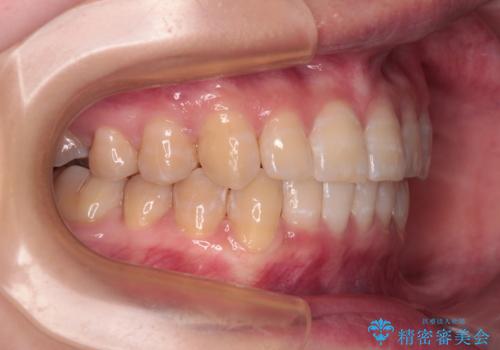

- 下顎の八重歯を気にして来院された患者様です。

マウスピース矯正でもワイヤー矯正でも対応可能であり、マウスピースによる治療を希望されたため、インビザラインを用いることとしました。

下顎前歯にデコボコが集中していたため、顎間ゴムによる後方移動とIPR(歯と歯の間を削ること)により歯列を整えることとしました。

下顎前歯のデコボコが集中しており、奥歯の咬み合わせは、上顎に対して下顎が前方位にある状態でした。下顎の歯列を後方へ移動させる治療はインビザラインの得意とするところですので、1年程度で無事に治療を終えることができました。